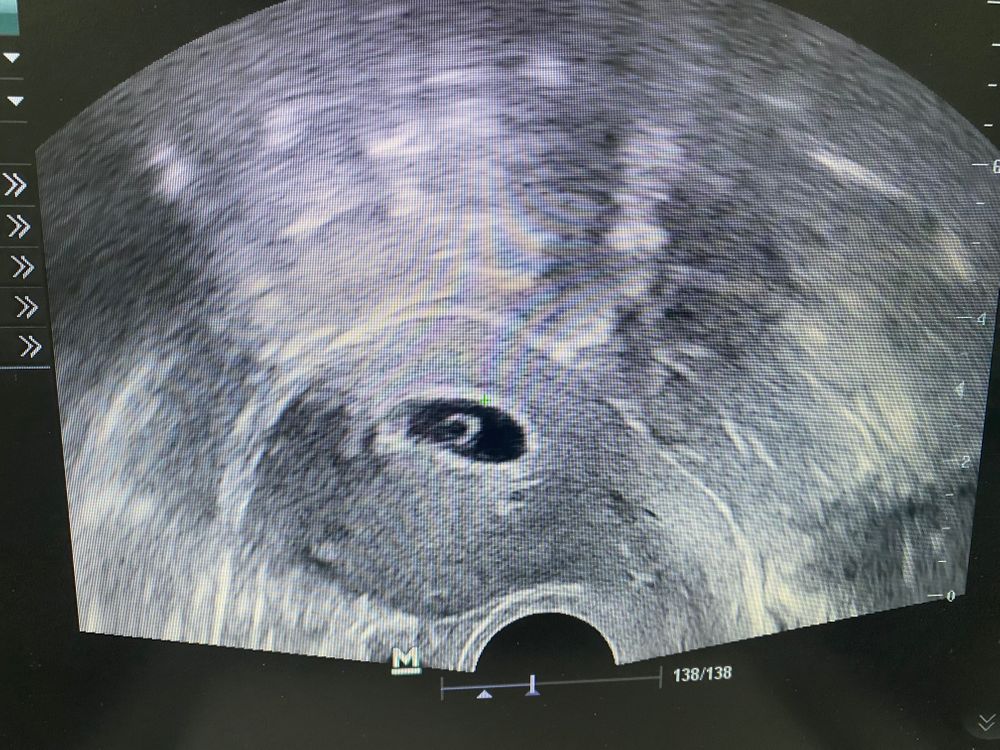

была у ре на плановом приеме, очень быстро посмотрела она меня по узи, буквально 5-10 секунд.

В общем беременность маточная, эмбрион визуализируется. Никаких размеров и тд не сказала (очень странно конечно) …

фото моей крошки 🥰🥰🥰